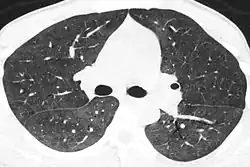

КТ-картина пневмоцистной пневмонии: диффузно-мозаичное «матовое стекло».

Диагноз устанавливается на основании данных рентгенографии и, предпочтительно, компьютерной томографии, демонстрирующей картину диффузных или диффузно-мозаичных зон снижения воздушности лёгочной ткани по типу «матового стекла». На этом фоне оксигенация артериальной крови значительно ниже ожидаемой при наблюдающейся клинической картине. Диагноз подтверждается обнаружением предполагаемого патогена в мокроте или при исследовании бронхоальвеолярного смыва. При микроскопии окрашенного материала обнаруживаются характерные кисты[5], имеющие вид «раздавленных шариков для пинг-понга». При микроскопии биоптата лёгкого выявляется утолщение альвеолярных перегородок с «пушистым» эозинофильным экссудатом в просвете альвеол.